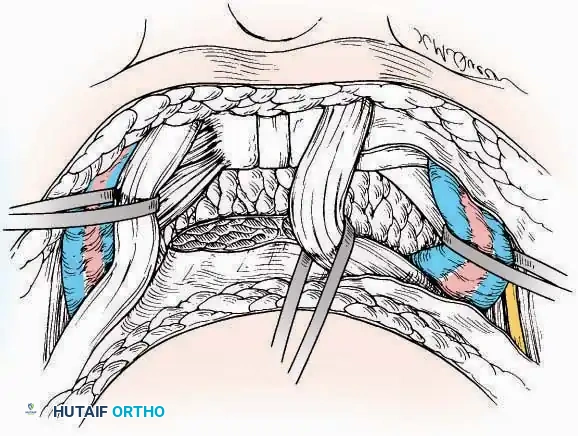

Medial Approach

Indications: Hallux valgus correction (bunionectomy), first MTP arthrodesis, or cheilectomy.

Surgical Technique:

* Incision: Make a curved incision 5 cm long on the medial aspect of the joint. Begin just proximal to the IP joint, curve it over the dorsum of the MTP joint (medial to the extensor hallucis longus [EHL] tendon), and terminate on the medial aspect of the first metatarsal 2.5 cm proximal to the joint.

* Superficial Dissection: As the deep fascia is incised, identify and laterally retract the medial branch of the first dorsal metatarsal artery and the medial branch of the dorsomedial nerve (a terminal branch of the superficial peroneal nerve).

* Deep Dissection: Dissect the fascia from the dorsum down to the bursa overlying the medial eminence of the metatarsal head.

* Capsulotomy: Make a curved incision through the bursa and joint capsule. Begin dorsomedially, continue proximally dorsal to the metatarsal head, sweep plantarward, and end distally on the medioplantar aspect of the joint. This creates an elliptical, racquet-shaped flap attached at the base of the proximal phalanx.

⚠️ Surgical Pitfall

While distal reflection of this racquet flap provides ample exposure of the first MTP joint, the extensive subfascial undermining required can compromise the vascularity of the skin flap, leading to delayed healing or necrosis. Consequently, the dorsomedial approach is often preferred in modern practice.

Dorsomedial Approach

Indications: Preferred approach for primary and revision first MTP arthroplasty, arthrodesis, and complex bunion corrections due to superior angiosome preservation.

Surgical Technique:

* Incision: Begin just proximal to the IP joint and extend proximally for 5 cm, running parallel and strictly medial to the EHL tendon.

* Exposure: Divide the superficial fascia. Identify and retract the EHL tendon laterally.

* Capsulotomy: The capsule can be incised longitudinally in the exact plane of the skin incision, allowing for subperiosteal elevation of the capsule medially and laterally, preserving the vascular supply to the medial skin flap.